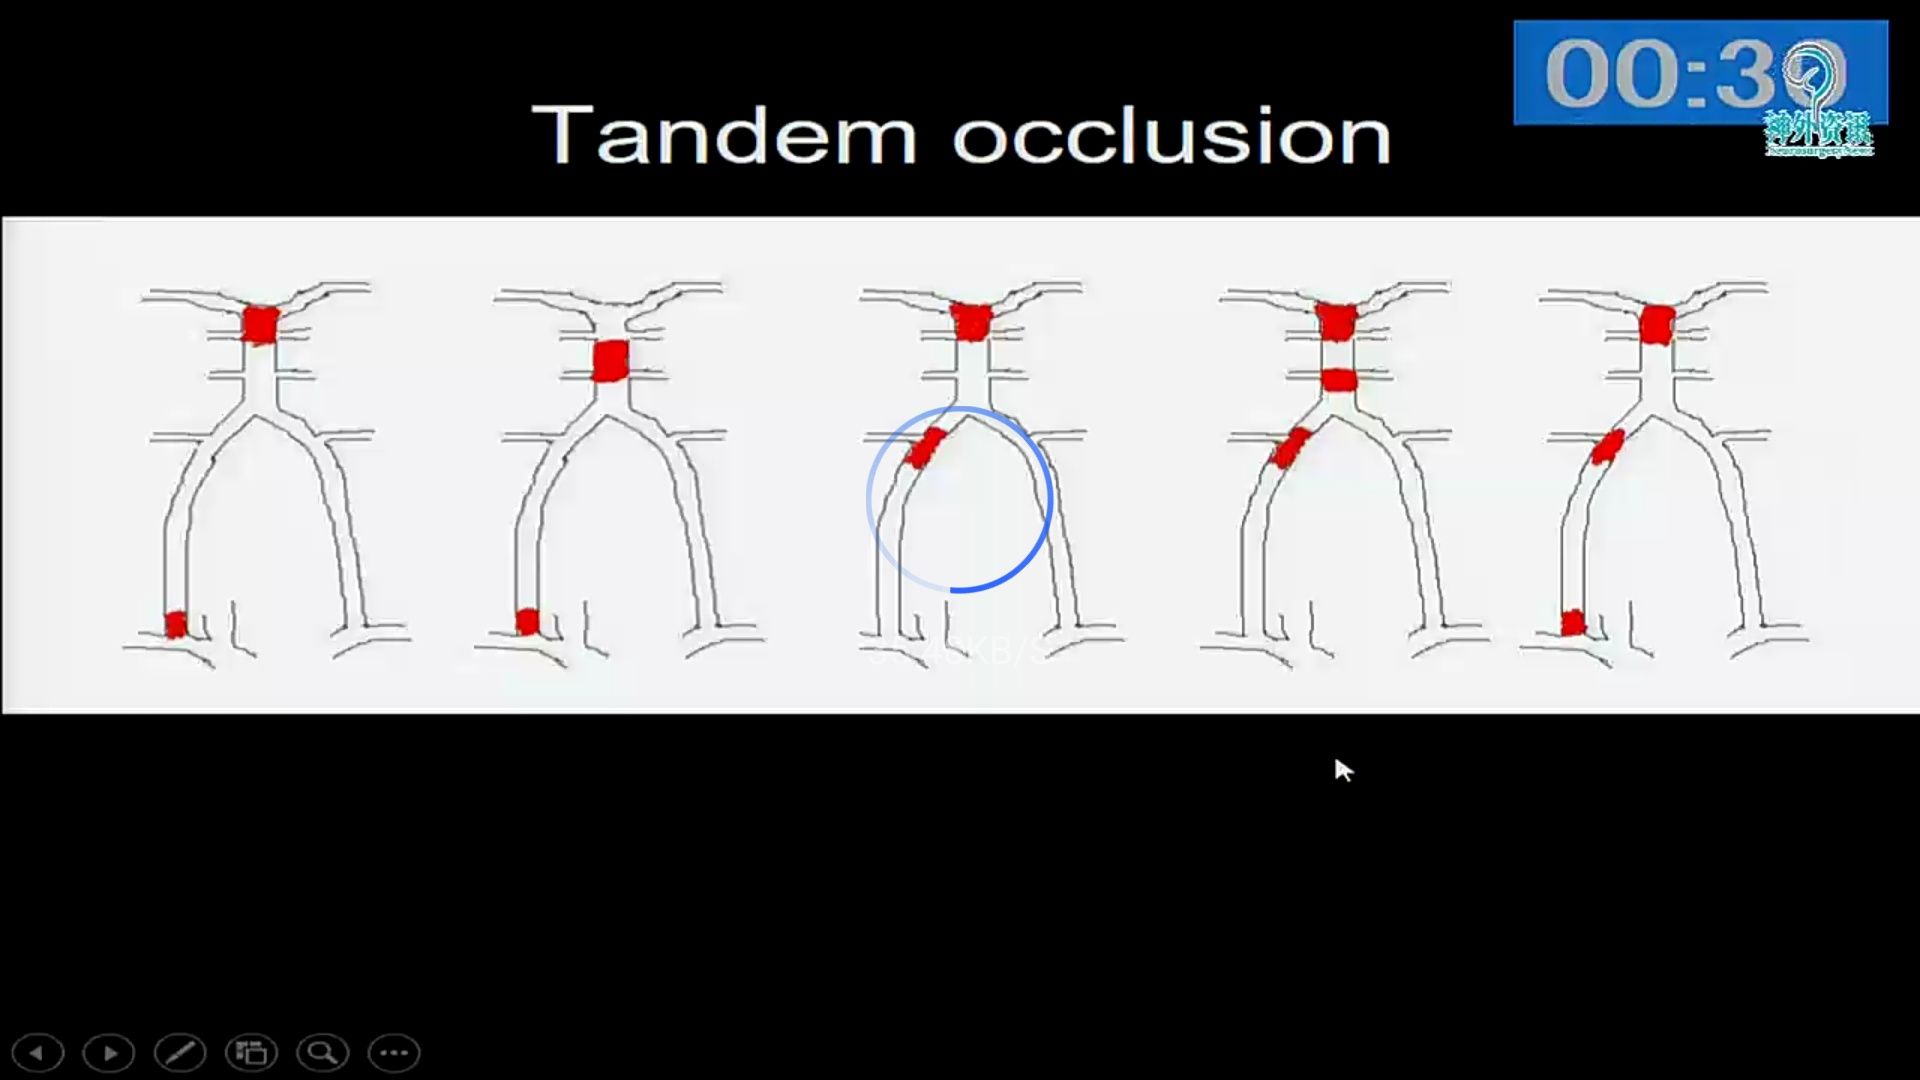

急性椎基底动脉闭塞血管内治疗